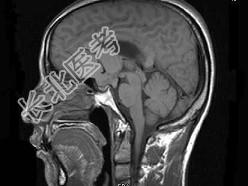

- 单项选择题男,32岁, 头痛,头昏半年, 加重10天伴抽搐,根据所提供图像, 最可能的诊断是 ( )

A、胶质瘤

B、颅咽管瘤

C、蛛网膜囊肿

D、表皮样囊肿

E、胆脂瘤